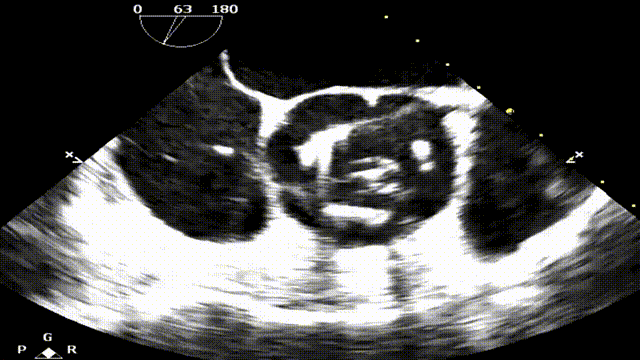

食道超声显示瓣架圆形展开,位置合适,未见显著反流:

台上复查食道超声,瓣架圆形展开,启闭良好:

食道超声瓣架位置正确,启闭良好,未见明显瓣周漏: